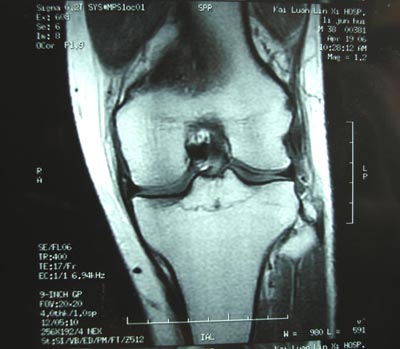

男,45。骑摩托车摔伤左膝肿痛三天,浮髌(+),活动受限。请大家看看片子有问题吗?

标题: 现将mri结果公布

手术证实是后交叉韧带胫骨附着处撕脱骨折。

术中用可吸收螺钉固定。